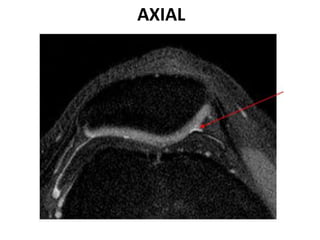

AXIAL

CONDROMALÁCIA PATELAR

 Lesão na cartilagem articular até a superfície óssea devido

ao excesso de forças de cisalhamento entre a patela e a

porção distal do fêmur.

 Comum em jovens e adultos.